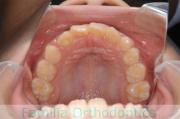

上顎

下顎